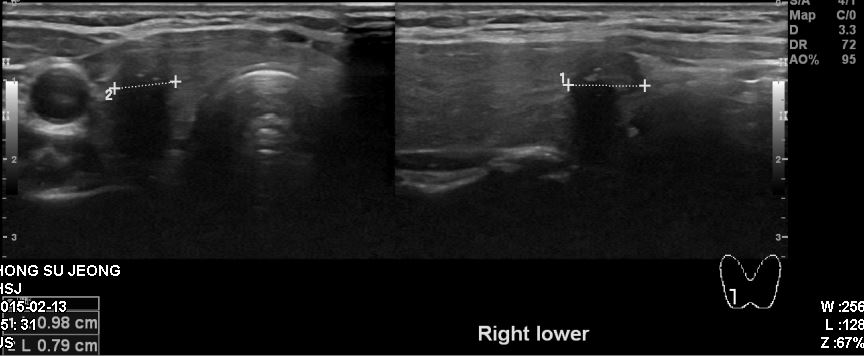

검진상 이상 소견으로 정밀검사 위해 내원하신 50대 여성 분으로  본원 조직 검사상 우측

갑상선 유두암 진단 되셨습니다.